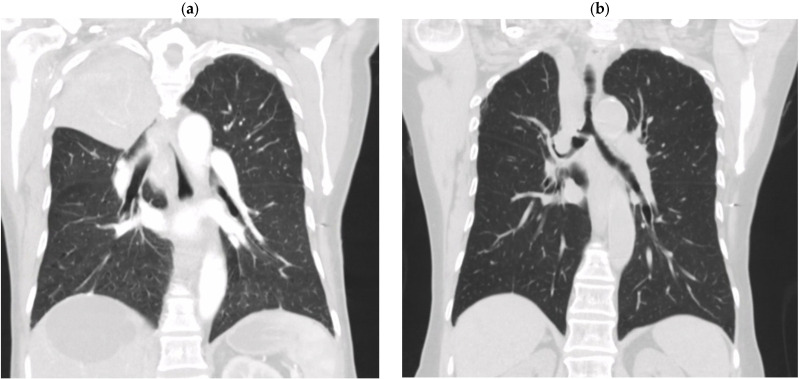

Anticytokine autoantibodies (AAbs), particularly anti-interferon-gamma (anti-IFN-γ) AAbs, disrupt cytokine functions, leading to infections, autoimmune-like diseases, and conditions resembling interleukin-12 (IL-12)/IFN-γ pathway defects. Advances in genetic testing have clarified overlaps between autoinflammatory, autoimmune disorders, and primary immunodeficiencies but reveal complex phenotypes and pathways. While these insights deepen our understanding of immune mechanisms, they also complicate diagnosis and treatment, with limited options for IFN-γ deficiencies caused by genetic mutations. The adult-onset immunodeficiency with disseminated lymphadenitis due to nontuberculous mycobacteria (NTM) and other opportunistic infections has been linked to high levels of anti-IFN-γ AAbs. This syndrome, initially identified in HIV-negative Asian patients, frequently affects individuals of Asian descent and may be associated with specific human leukocyte antigen (HLA) alleles. The presence of neutralizing anti-IFN-γ AAbs impairs the IFN-γ-dependent immune response, likely contributing to the persistent NTM infection. This study underscores the potential for late-onset anti-IFN-γ AAb syndrome to manifest with disseminated NTM (dNTM) infections, highlights the importance of timely diagnosis and considers rituximab as a potential therapeutic option.